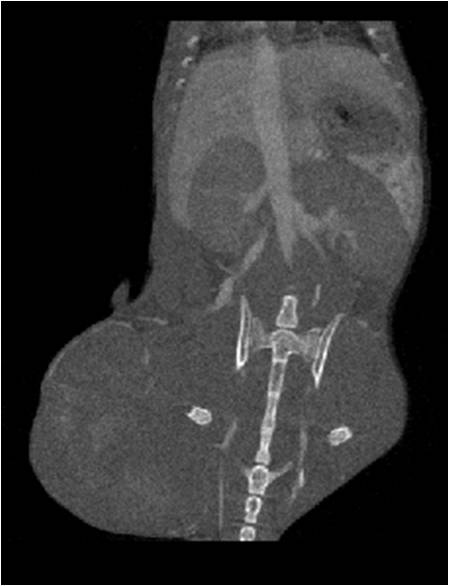

腫瘤血管生成

肺纖維3.jpg

肺轉(zhuǎn)移

小鼠模式,22.5μm像素

正常

正常.jpg

8天                                                                  14天

8天.jpg  14天.jpg

無造影劑注入                                     造影劑注入

心血管

胸部和心血管的層析成像                                       胸部和心血管的3D圖像

心血管.jpg     心血管1.jpg